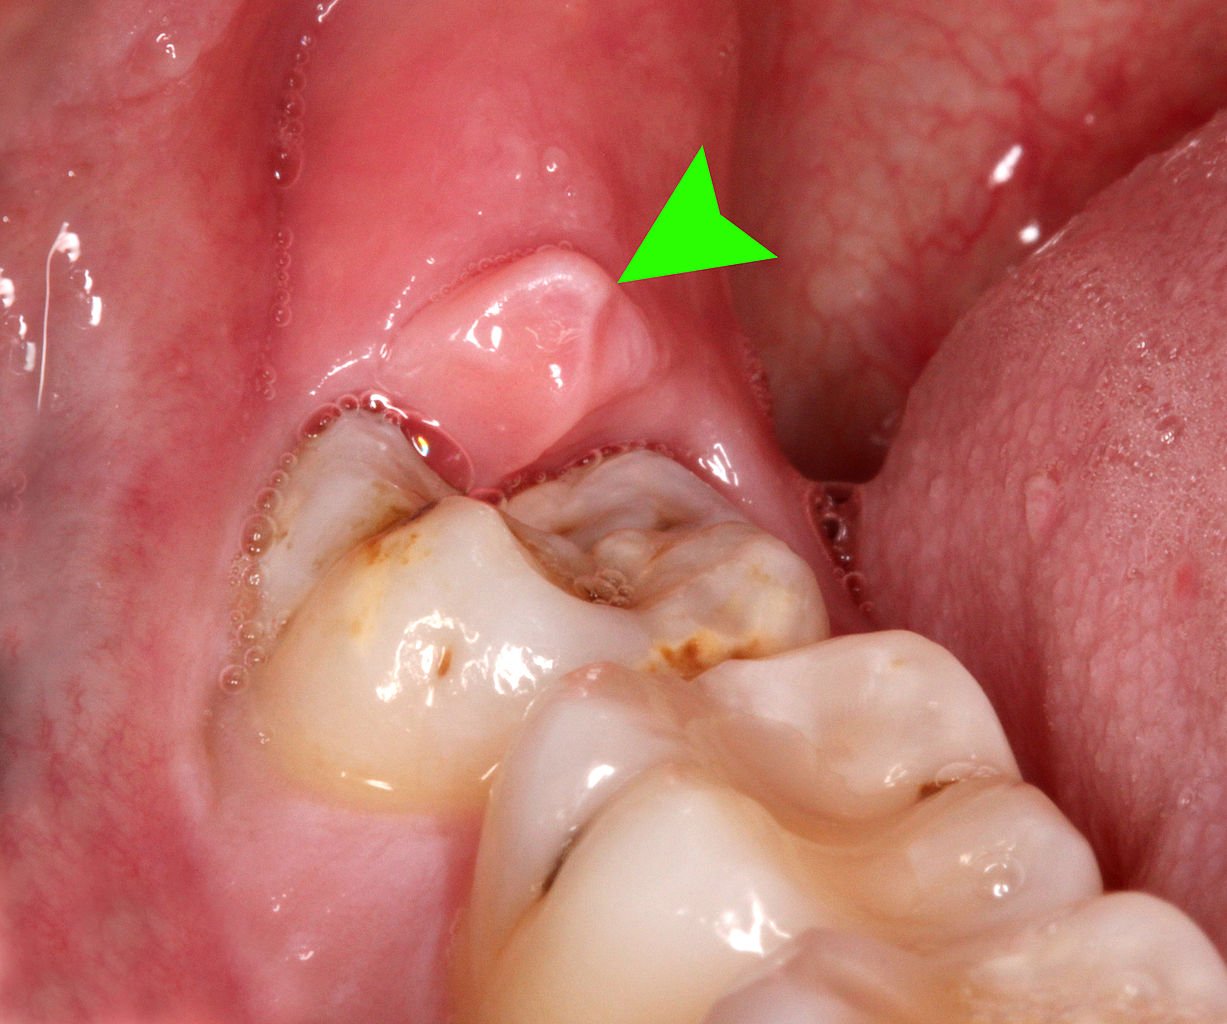

Abcesul dentar este caracterizat prin aparitia unei pungi cu puroi in interiorul tesuturilor din jurul unui dinte. Aceasta infectie la baza dintelui se manifesta printr-o tumefactie care se dezvolta la gingie si deformeaza intreaga regiune in care este localizat. Semnele vizibile sunt tesutul rosu, tensionat si congestionat care acopera partea exterioara a gingiei.

In plus, abcesul se poate sparge si din acesta va curge puroi si sange. Alte simptome pot fi: schimbarea culorii dintelui in roz sau gri, umflaturi in tesutul gingiei din apropierea dintelui sau senzatia ca dintele este impins afara din locul sau si nu permite gurii sa se inchida in mod corect.

- Cel gingival: abcesul se gaseste numai in tesutul gingival si nu afecteaza ligamentul periodontal sau dintele in sine